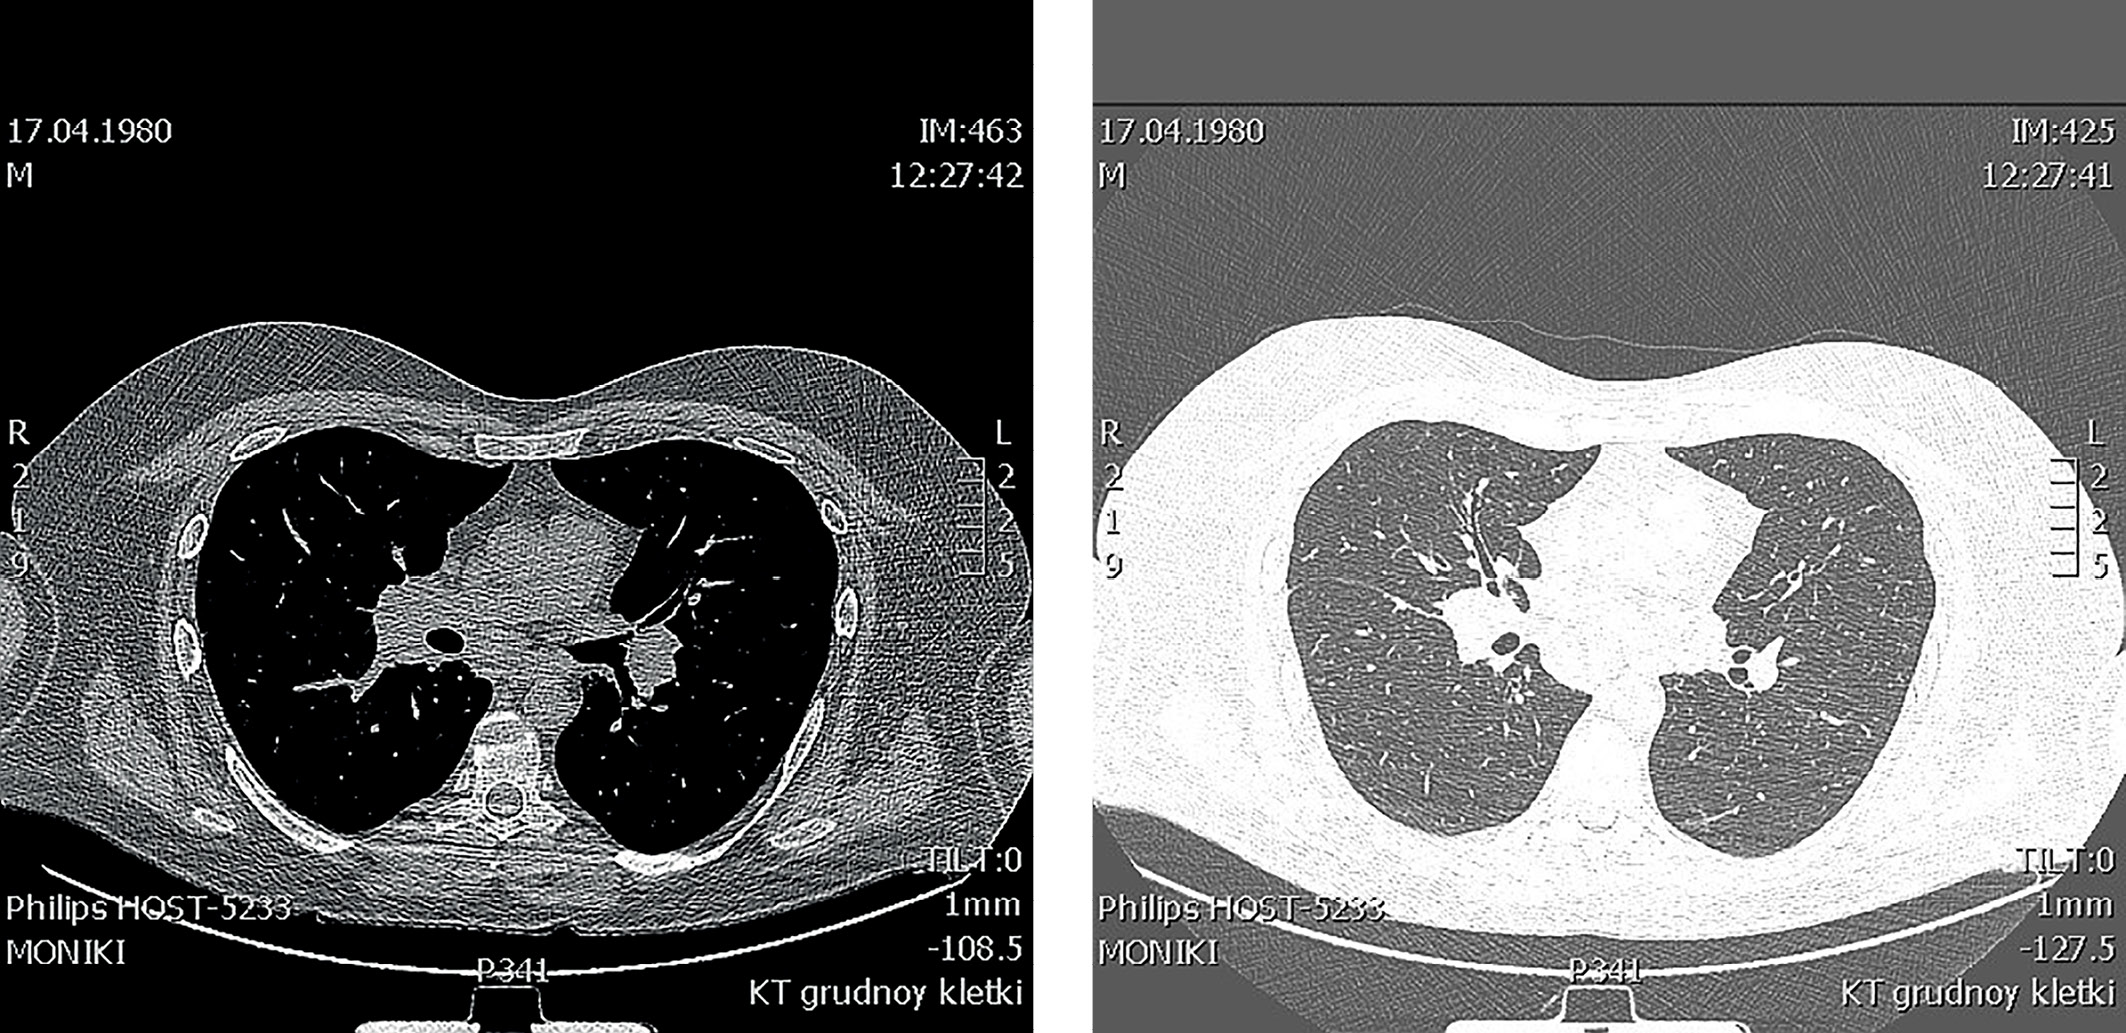

Рисунок 4, 5. КТ органов грудной клетки от 2018г.

(Увеличение лимфоузлов средостения (паратрахеальных и бифуркационных)).

Figure 4, 5. CT scan of the chest organs from 2018

(Enlarged mediastinal lymph nodes (paratracheal and bifurcation))